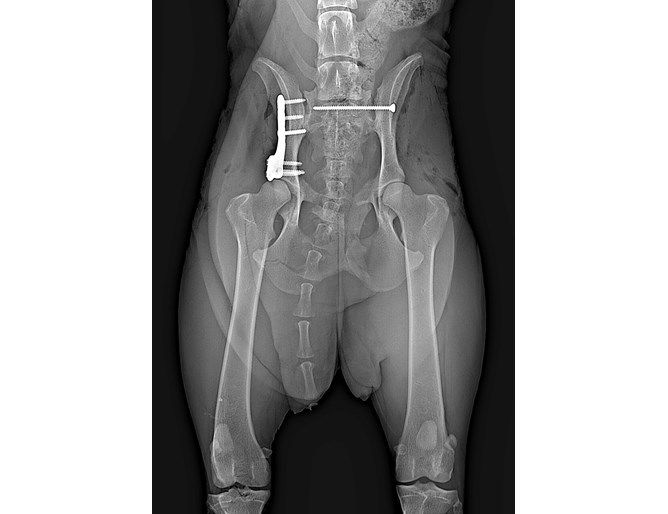

Роска е претърпяла операция за спасяване на таза и са ѝ поставени метални пластини. Лекарите от клиниката вярват, че няма да е необходима втора интервенция. След изписването си кучето ще бъда отглеждано в приемен дом от Росица Идакиева. Жената е активист на „Четири лапи“ и е с голям опит в грижите за пострадали животни.